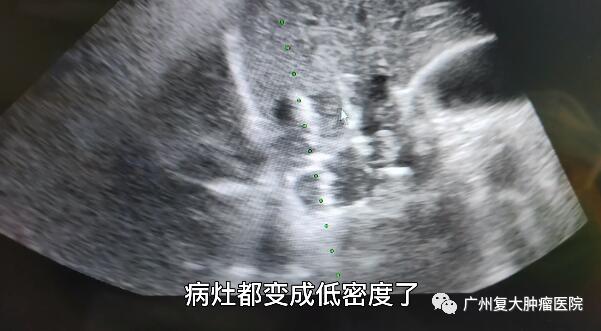

入院后,患者完善相關檢查。結合患者病史,為進一步控制腫瘤生長,減輕腫瘤負荷,延長患者生命,再次明確腫瘤類型,方便下一步指導用藥。經患者及家屬理解與同意后,在超聲影像引導下,我院牛立志院長為其實行肝臟腫瘤穿刺活檢及不可逆電穿孔消融術。“病灶變成低密度,表明腫瘤得到一個比較完全的消融?!?/p>